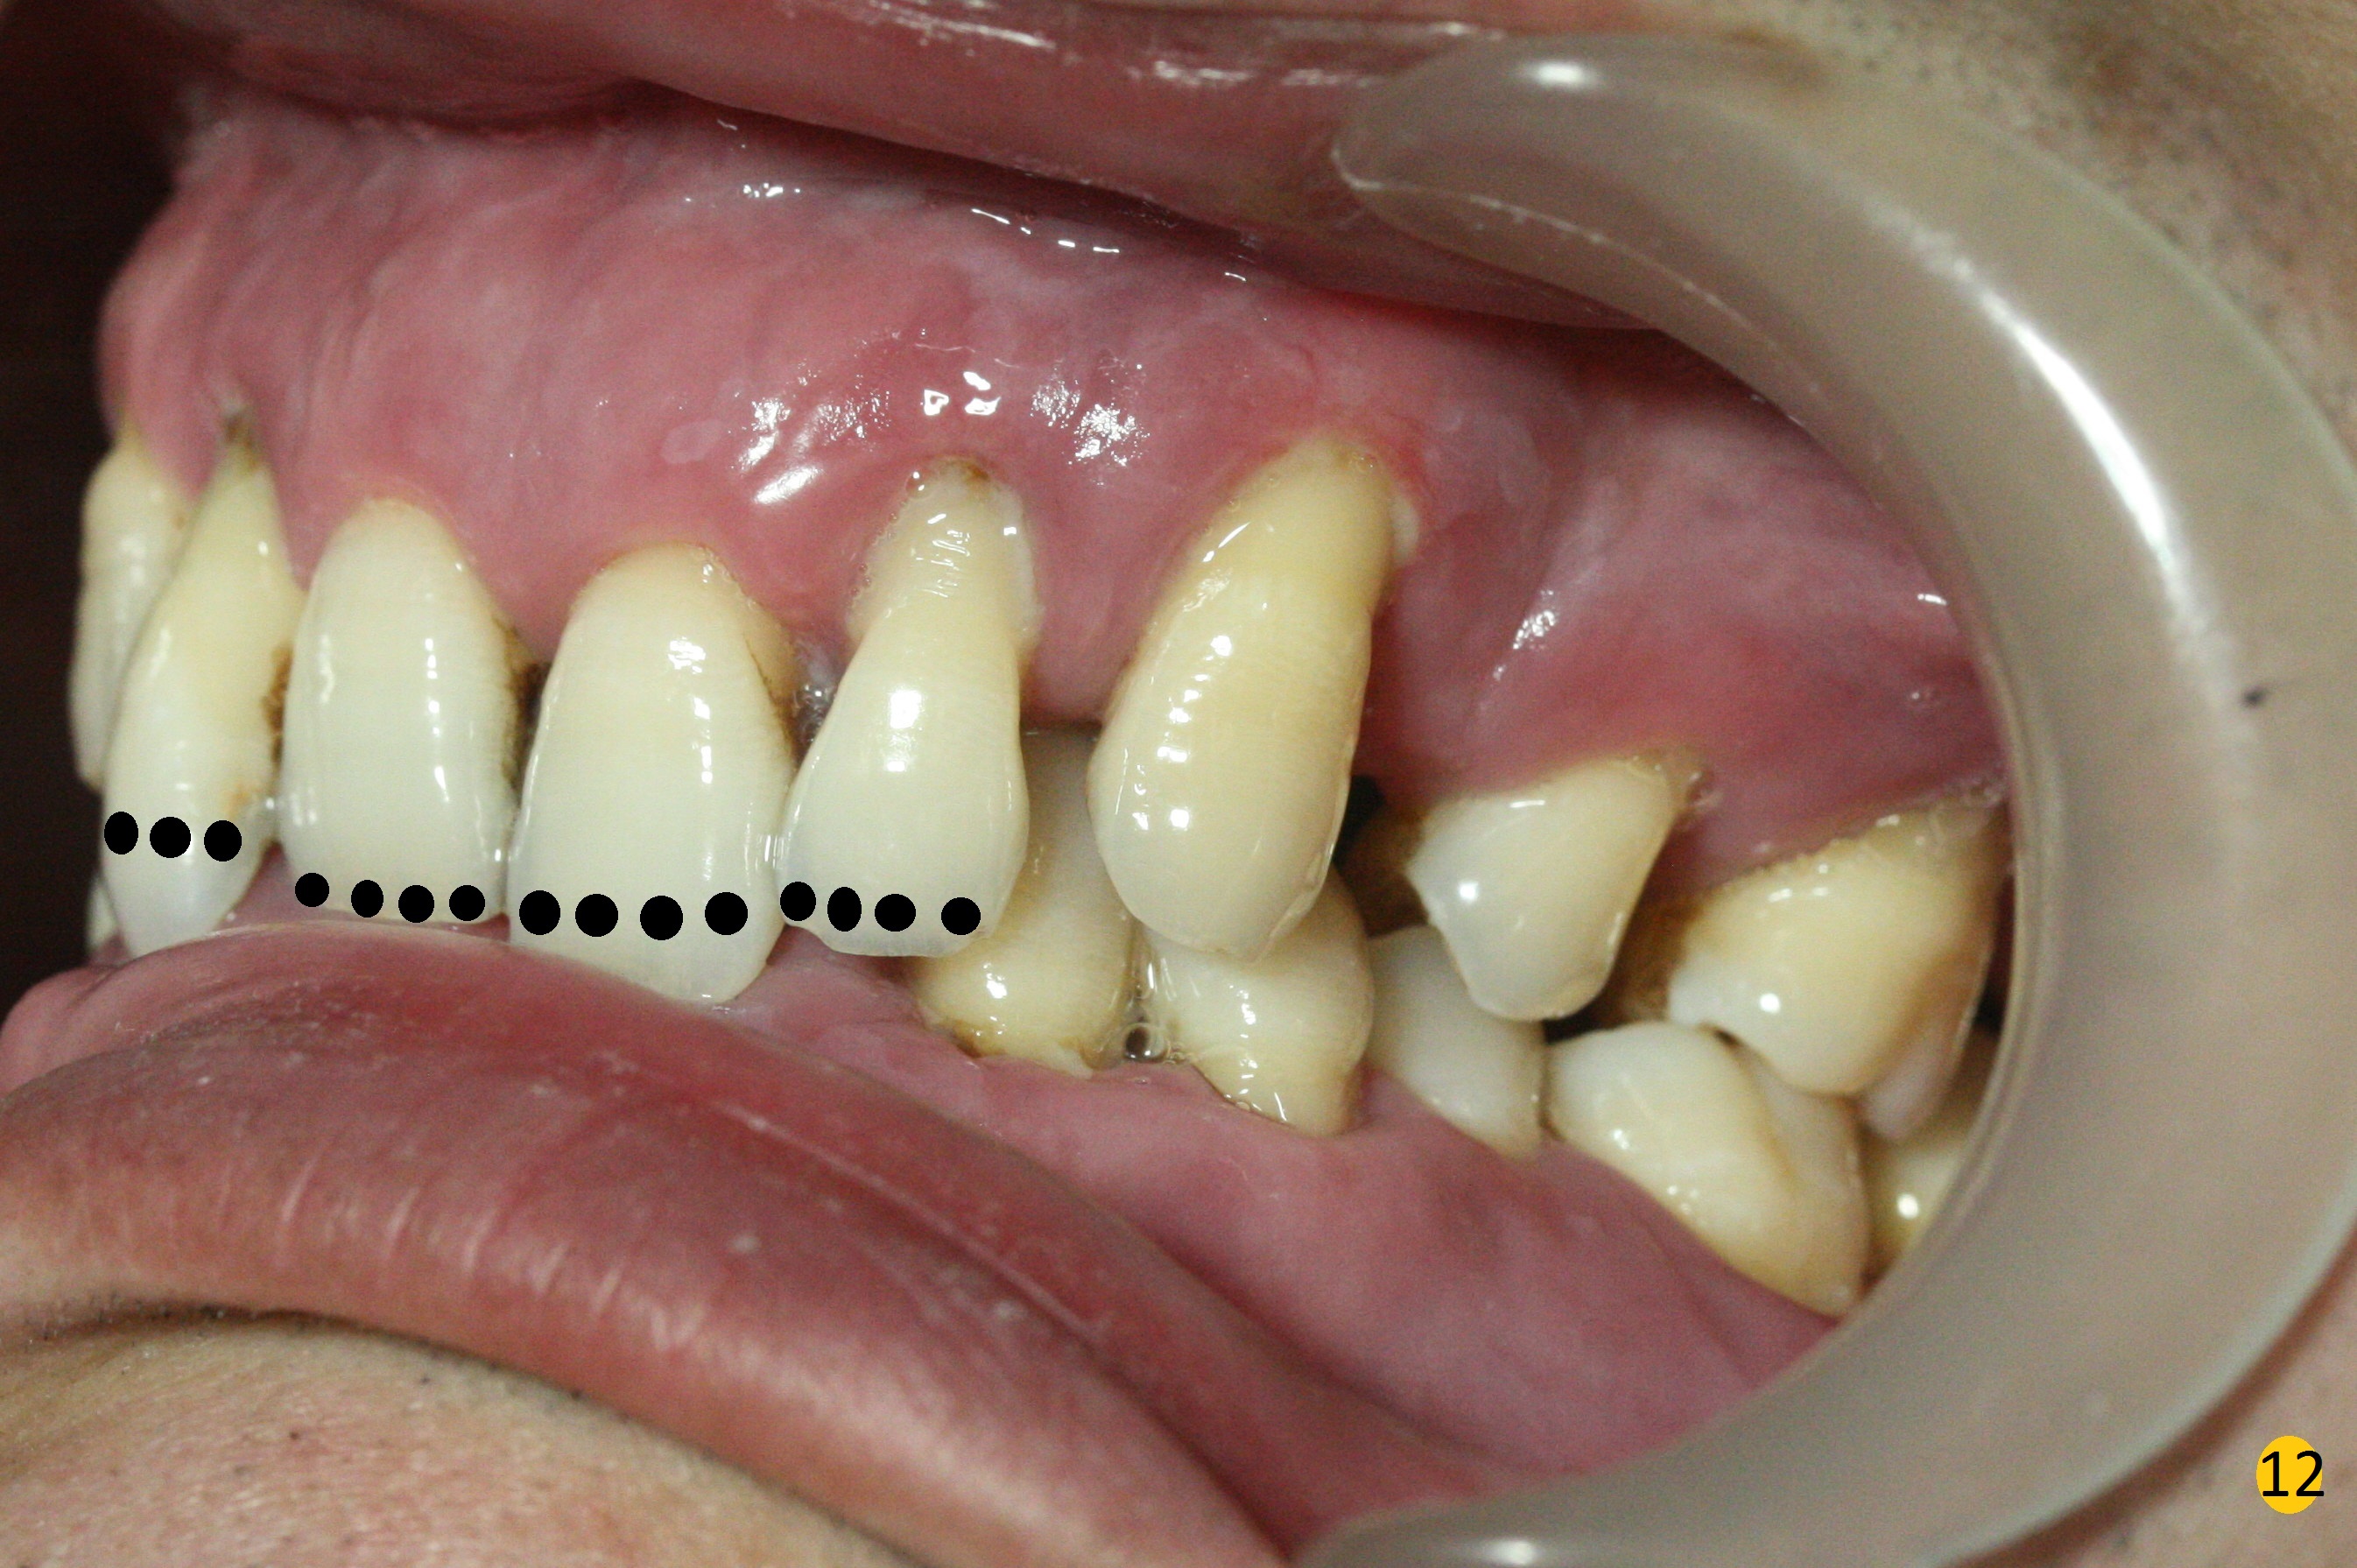

Class II Division II malocclusion (Fig.2,6) will make it difficult to restore #23-26 implant-supported FPD. Although the teeth #7-10 may need to be replaced later (Fig.7,8), enameloplasty will be conducted for #7-10 (Fig.9 white area; Fig.12 black circles (gross reduction)) prior to #23-26 extraction and implant placement (Fig.10). To be flexible in restoration (angulation) and possible future hybrid denture, 2-piece narrow implants will be placed (3.0 or 3.3 mm) instead of 1-piece ones. In fact CBCT shows that the narrowest regular implant (3.8 mm) can be placed in the lower anterior region (Fig.13-15).